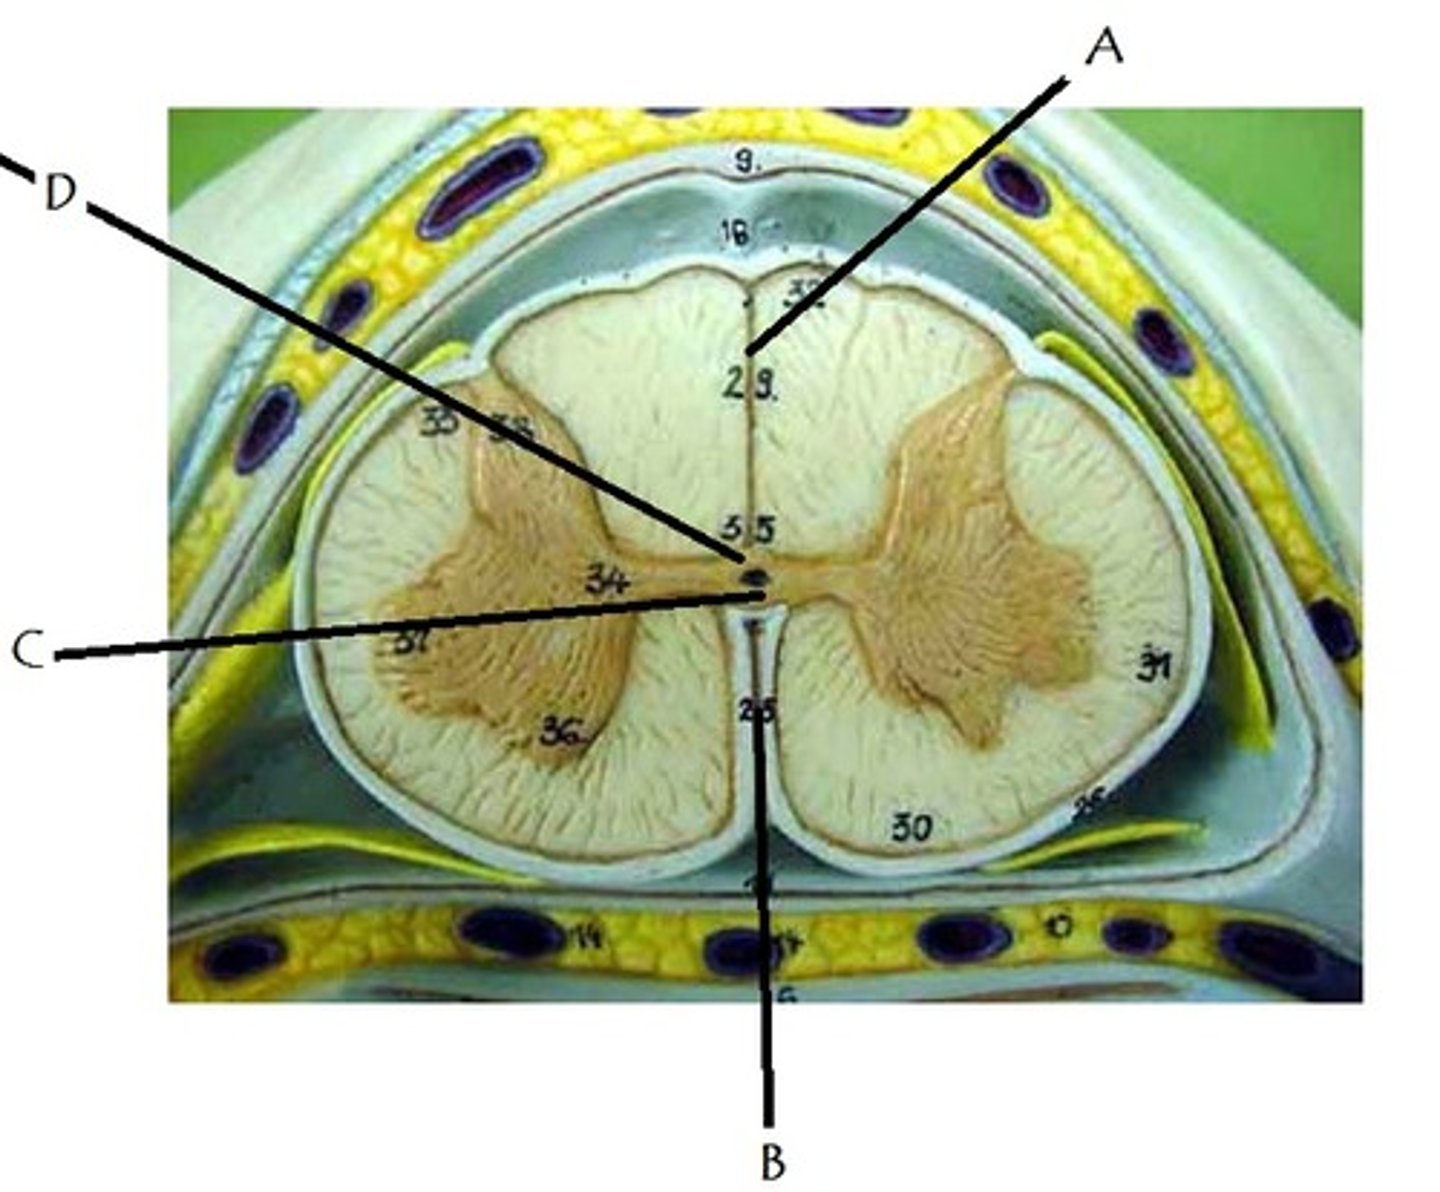

Identify A

lateral gray horn

Identify B.

anterior gray horn

Identify C.

Identify B

posterior median sulcus